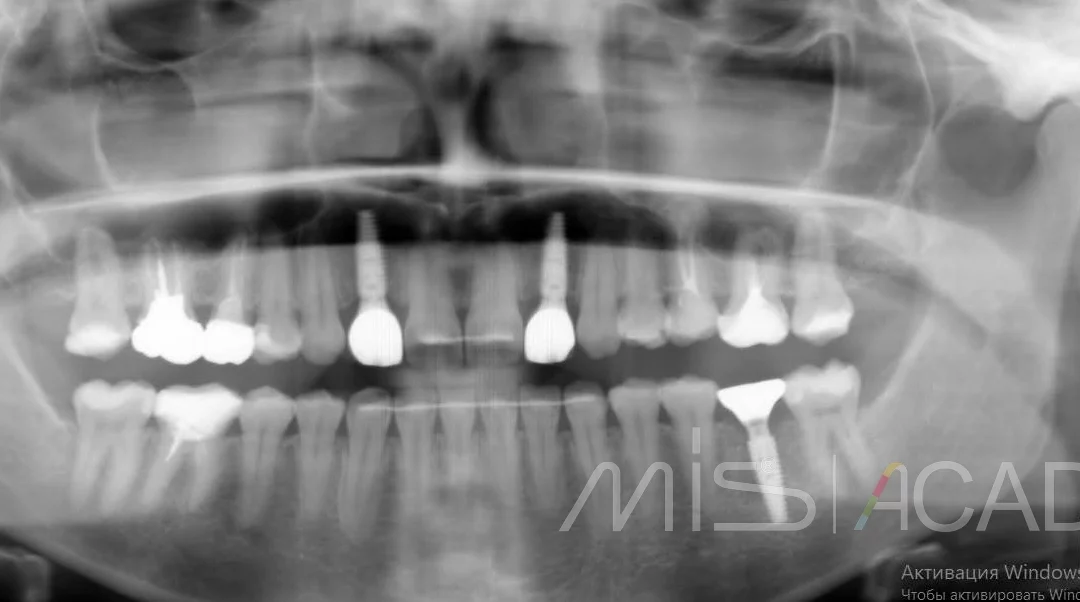

Юрий Гузеев | Клинический кейс YG-130

Подвижность зубов, периодонтальные изменения. - Удаление, имплантация MIS C1 . - Два трансплантата. - Коронально смещенный лоскут для коррекция зенитов. - Connect абатмент + временные...